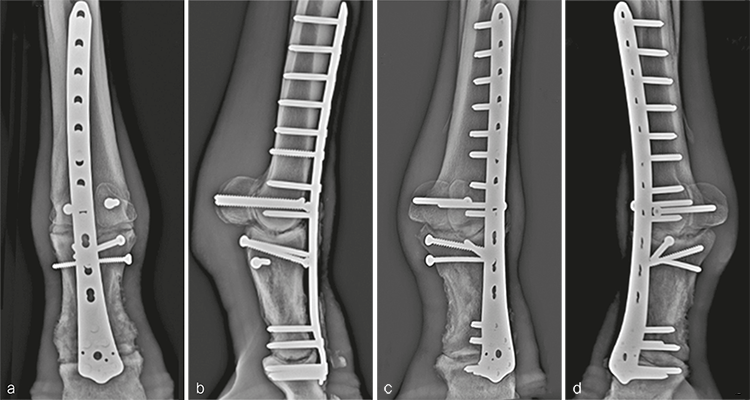

The plate was contoured to the desired 15 of dorsiflexion at the level of the fetlock joint to provide an appropriate joint angle (Fig 4a). Three, approximately 4 cm long dorsal midline incisions were performed through the skin and extensor tendon at the level of the proximal end of the plate, the metacarpophalangeal joint, and at the distal end of the plate overlying the proximal interphalangeal joint. Using a combination of sharp dissection and a large periosteal elevator, a tunnel was created between the bone and overlying soft tissues including the extensor tendon. The plate was inserted into the tunnel and appropriate plate positioning, and cortical alignment were confirmed radiographically. A Push-Pull Reduction Device was placed through hole (A) in the head of the plate at the level of the proximal interphalangeal joint to compress the plate onto the dorsal cortices of the phalanges and maintain alignment of the proximal interphalangeal joint. Five 5.0 mm locking screws were inserted in the expanded head of the plate to purchase the distal aspect of P1 and the proximal aspect of P2. To ensure plate-bone contact proximally, two 5.5 mm cortex screws were placed into the distal aspect of the metacarpus (plate shaft holes 4 and 5). The remaining holes overlying the metacarpus were filled with 5.0 mm locking screws; where possible, 4.5 mm cortex screws were placed through the plate overlying large fragments of the P1. Finally, two 5.5 mm cortex screws were placed in lag fashion abaxial to the plate to engage the medial and lateral proximal sesamoid bones (Fig 5). Screws placed outside of the dorsal midline incisions were placed through additional stab incisions.

The incisions were closed routinely (Fig 4b). The distal limb was placed in a cast, and the patient was assisted in recovery. Surgery time, including casting, was 310 minutes.